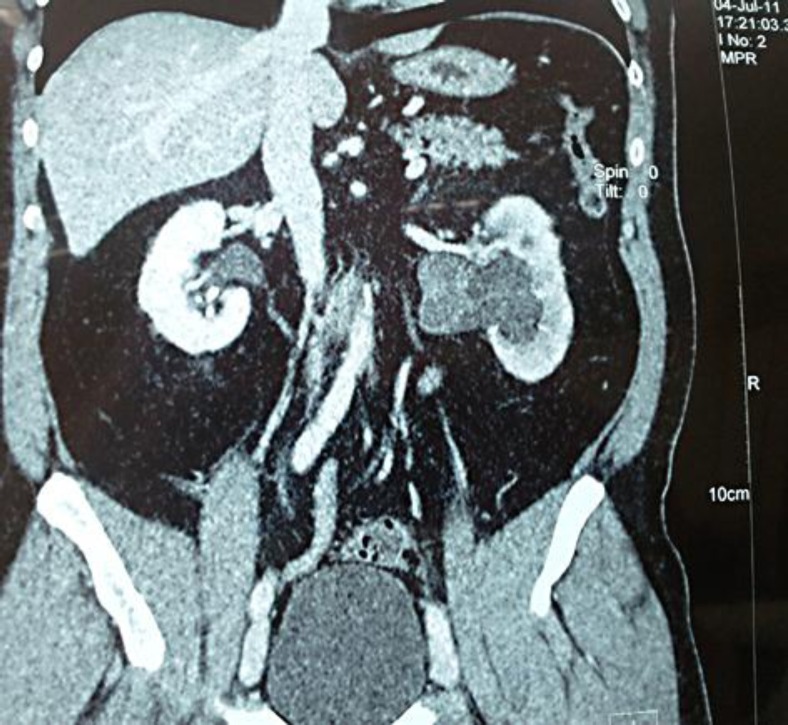

发生在泌尿生殖系统的肉瘤十分罕见,约占所有软组织肉瘤的2.1%,预后较差。肾肉瘤相当罕见,约占恶性肾病例的1-3%。肾脏低级别纤维黏液样肉瘤(LGFS)是一种非常罕见的,惰性但转移的软组织肉瘤,具有看似良性的组织学特征。估计5年总生存率超过90%,但可能发生很晚的局部复发和远处转移,这强调了长期随访的必要性。我们报告一例48岁男性患者的LGFS位于肾盂。这可能是第一次报道起源于肾盂的LGFS。

Sarcomas of the genitourinary tract are quite rare, accounting for 2.1% of all soft tissue sarcomas and have a poor prognosis. Kidney sarcomas are quite rare, representing 1–3% of malignant renal cases. Low-grade fibromyxoid sarcoma (LGFS) of the kidney is an exceedingly uncommon, indolent but metastasizing soft tissue sarcoma with deceptively benign-appearing histological features. The estimated 5-year overall survival seems to be over 90%, but very late local relapses and distant metastasis may occur, which underlines the need for a long-term follow-up. We present a case of a 48-year-old male patient with a LGFS located on the renal pelvis. This is probably the first report of LGFS arising from the renal pelvis.